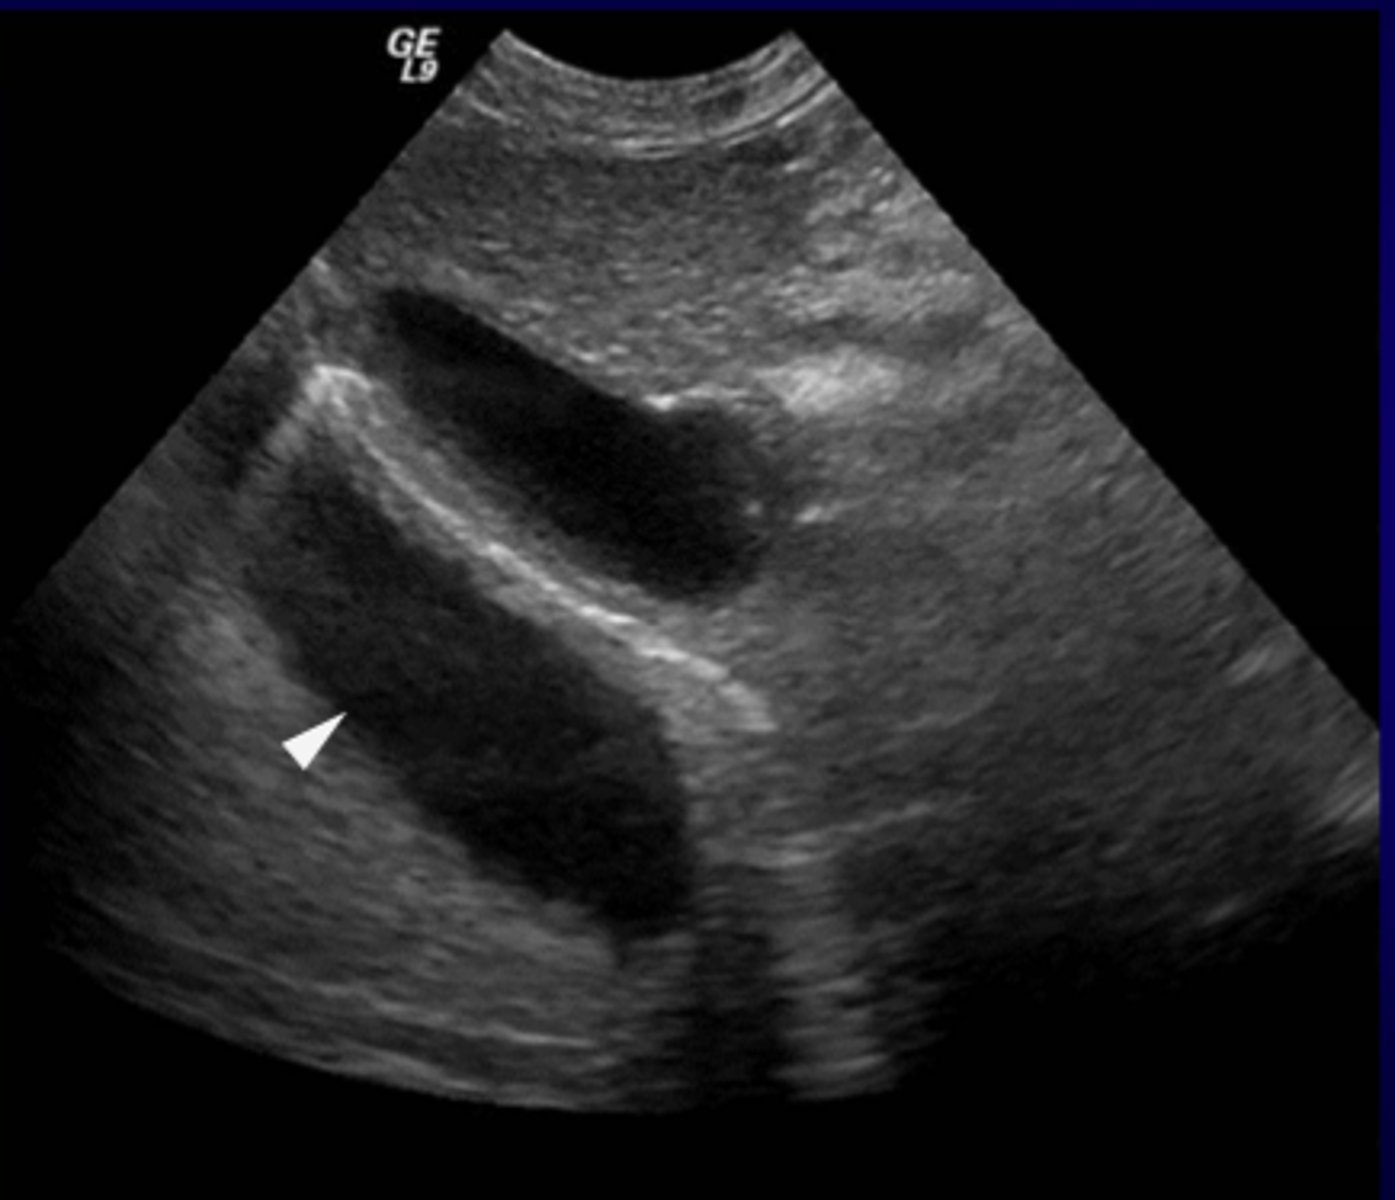

What ultrasound artifact causes the duplication of image of the opposite side of a strong reflector?

Mirror Image Artifact

Where is the Mirror Image Artifact most common?

What medium would be the strong reflector?

Thorax/Abdomen Interface

Diaphragm